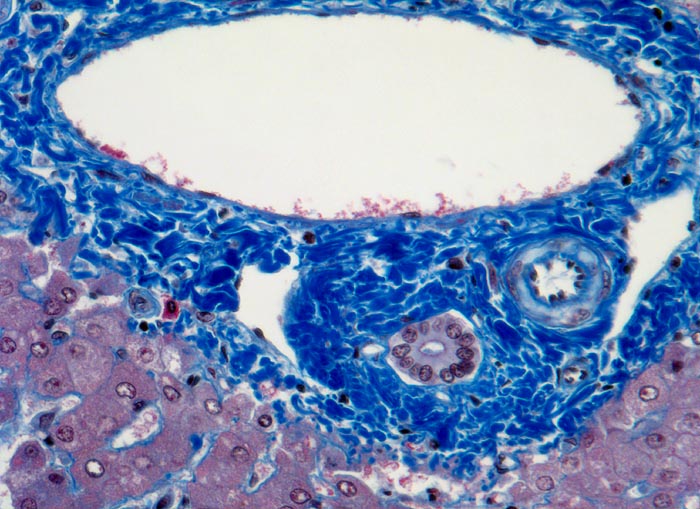

Meist findet sich eine grobtropfige oder gemischttropfige Verfettung des Parenchyms. Schon im Frühstadium der alkoholischen Steatohepatitis kann eine perizelluläre Maschendrahtfibrose, perisinusoidale und perivenuläre Fibrose mit Beginn in der Zone 3 festgestellt werden. Die Kombination von perivenulärer und perizellulärer (> 1096) Fibrose wird bei starker Ausprägung mit Arealen von dichter Kollagenfaserbildung auch als zentrale sklerosierende hyaline Nekrose bezeichnet. Wenn der Vernarbungsprozess fortschreitet, kann die perivenuläre Fibrosezone mit vernarbten Portalfeldern verschmelzen. Zentralvenen verschwinden oder sind stark in der Anzahl reduziert. Eine Phlebosklerose oder Obliteration der Zentralvenen kann hinzukommen. Breite Bänder von fibrotischem Gewebe mit Ductulusproliferationen und gemischtem Entzündungsinfiltrat umgeben die bei alkohlischer Zirrhose meist kleinen Regeneratknoten (=mikronoduläre Leberzirrhose mit Regeneratknoten von weniger als 3mm Durchmesser). Bei längeren Abstinenzphasen kann sich aufgrund der gesteigerten Regeneration auch eine gemischtknotige Zirrhose ausbilden. Ein gleichzeitiges Vorliegen einer Steatose oder Steatohepatitis (Steatose+neutrophile Granulozyten) in einer alkoholischen Leberzirrhose signalisiert in der Regel einen fortgesetzten Aethylabusus. Typisch für alkoholtoxische Leberschädigung sind Mallory-Denk Körperchen (> 3021), Megamitochondrien (> 3022) und eine Zellschwellung (=Ballonierung) aufgrund einer gestörten Albuminausschleusung. Oft können mässige Mengen von Hämosiderinablagerungen vor allem in den Kupffer Zellen nachgewiesen werden. Weitgehend identische morphologische Veränderungen wie bei der aethylischen Leberschädigung finden sich auch bei der nicht alkoholischen Steatohepatitis (NASH) d.h. bei Patienten, die keinen oder nur wenig Alkohol konsumieren.

• Breite Fibrosebänder mit Ductulusproliferation und gemischter Entzündung.

• Perivenuläre Fibrose und perizelluläre Maschendrahtfibrose in Zone 3.

• Verminderte Anzahl Zentralvenen.